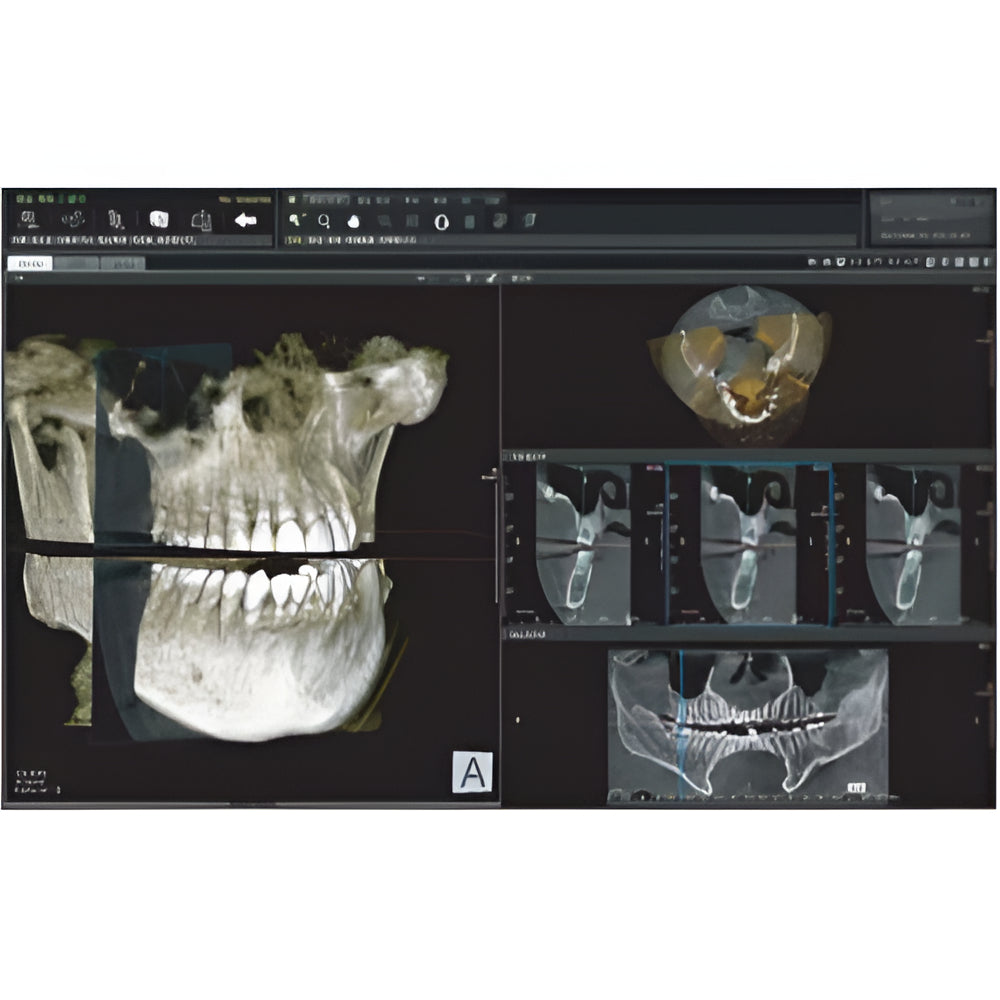

Genoray Papaya Plus Pan + CBCT (14x14 FOV)

Genoray Papaya Plus Pan + CBCT (14x14 FOV)

Papaya uses the CdTe sensor, which improves image quality while keeping radiation exposure to a minimum. The CdTe (Cadimium telluride) sensor overcomes the limitations of a CMOS sensor to always produce high quality images.

- 3D imaging software

- Field Of View: 4x5, 7x7, 8x8, 14x8, 14x14